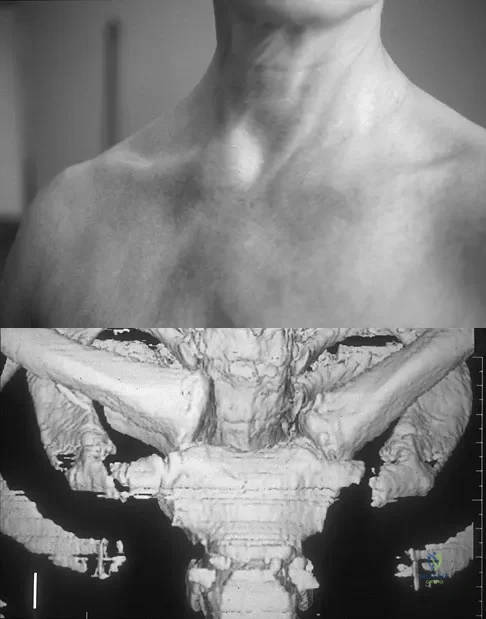

Question 100

Figure 11a shows the clinical photograph of a 46-year old woman who reports a 3-week history of pain and a "lump" at the base of her neck. She is otherwise in good health and denies any trauma. A 3-D reconstruction CT is shown in Figure 11b. What is the most likely diagnosis?

Explanation